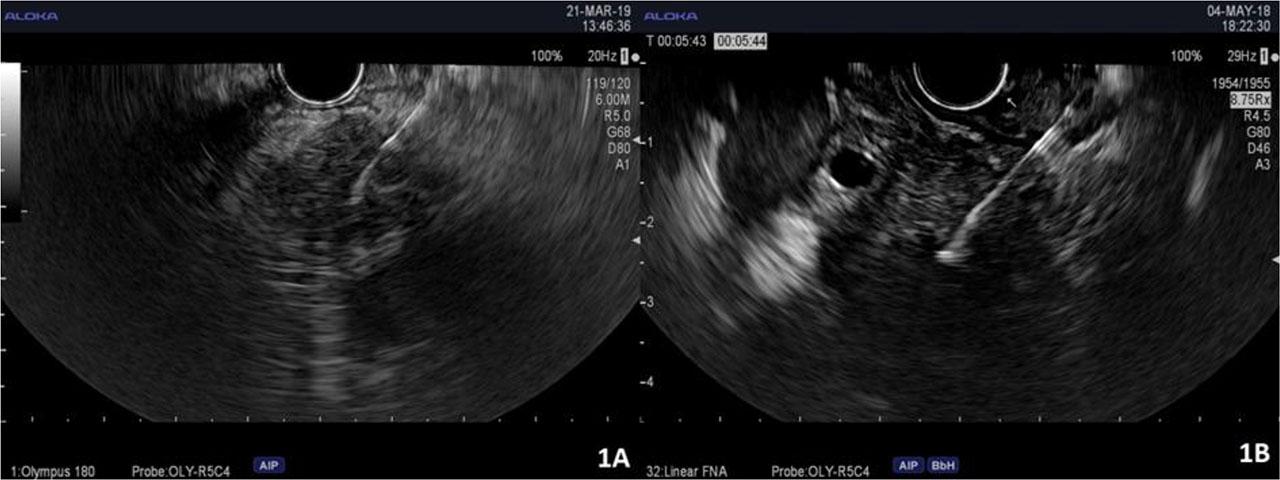

A total of 426 procedures were recorded for the 401 patients included in the study, out of which 334 were EUS-FNA and 92 EUS-FNB (Table 3). Both FNA and FNB were successful in the lot of patients (Figure 1). However, EUS-FNB exceeded EUS-FNA regarding the diagnostic yield (91.3% compared to 84.1%, p-value<0.05). In addition, the number of passes for the FNA procedures was on average 1.99 per case, compared to a significantly lower mean of 1.63 passes for each FNB procedure (p-value<0.05).

FNA (1A) and FNB (1B) EUS-guided biopsies from pancreatic tumors.